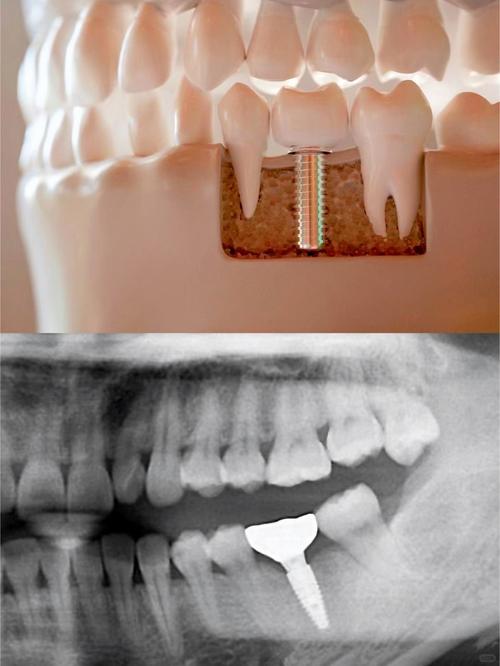

- 种植牙是一种替代缺失牙齿的方法。

- 它通过外科手术将一个纯钛制成的金属种植体(人工牙根)植入到你的牙槽骨中。

- 等种植体与牙槽骨牢固结合(骨结合)后,在种植体上方安装一个基台,最后在基台上安装一个牙冠,看起来和功能都像真牙。